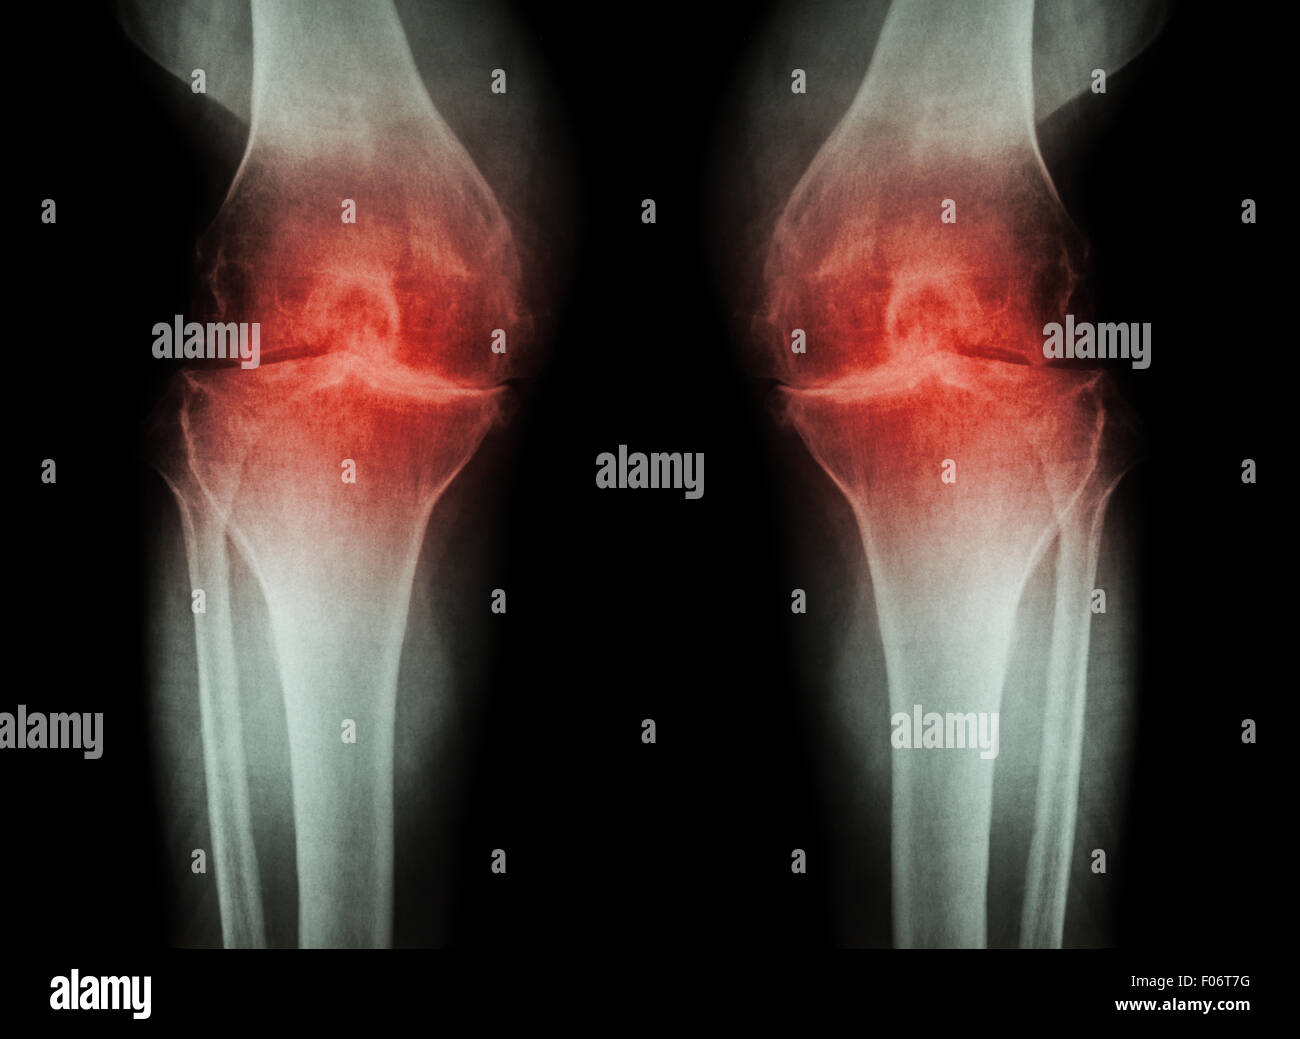

L'ARTHROSE DU GENOU Arthrose du genou ( ) ( Film x-ray à la fois avec l'arthrite du genou d'articulation du genou : articulation du genou espace ) ( Médecine et Sc Banque D'Imageshttps://www.alamyimages.fr/image-license-details/?v=1https://www.alamyimages.fr/photo-image-l-arthrose-du-genou-arthrose-du-genou-film-x-ray-a-la-fois-avec-l-arthrite-du-genou-d-articulation-du-genou-articulation-du-genou-espace-medecine-et-sc-86202573.html

L'ARTHROSE DU GENOU Arthrose du genou ( ) ( Film x-ray à la fois avec l'arthrite du genou d'articulation du genou : articulation du genou espace ) ( Médecine et Sc Banque D'Imageshttps://www.alamyimages.fr/image-license-details/?v=1https://www.alamyimages.fr/photo-image-l-arthrose-du-genou-arthrose-du-genou-film-x-ray-a-la-fois-avec-l-arthrite-du-genou-d-articulation-du-genou-articulation-du-genou-espace-medecine-et-sc-86202573.htmlRFF06T79–L'ARTHROSE DU GENOU Arthrose du genou ( ) ( Film x-ray à la fois avec l'arthrite du genou d'articulation du genou : articulation du genou espace ) ( Médecine et Sc

L'ARTHROSE DU GENOU Arthrose du genou ( ) ( Film x-ray à la fois avec l'arthrite du genou d'articulation du genou : articulation du genou espace ) ( Médecine et Sc Banque D'Imageshttps://www.alamyimages.fr/image-license-details/?v=1https://www.alamyimages.fr/photo-image-l-arthrose-du-genou-arthrose-du-genou-film-x-ray-a-la-fois-avec-l-arthrite-du-genou-d-articulation-du-genou-articulation-du-genou-espace-medecine-et-sc-86202580.html

L'ARTHROSE DU GENOU Arthrose du genou ( ) ( Film x-ray à la fois avec l'arthrite du genou d'articulation du genou : articulation du genou espace ) ( Médecine et Sc Banque D'Imageshttps://www.alamyimages.fr/image-license-details/?v=1https://www.alamyimages.fr/photo-image-l-arthrose-du-genou-arthrose-du-genou-film-x-ray-a-la-fois-avec-l-arthrite-du-genou-d-articulation-du-genou-articulation-du-genou-espace-medecine-et-sc-86202580.htmlRFF06T7G–L'ARTHROSE DU GENOU Arthrose du genou ( ) ( Film x-ray à la fois avec l'arthrite du genou d'articulation du genou : articulation du genou espace ) ( Médecine et Sc